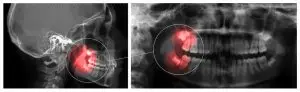

There are different levels of critical care with wisdom tooth emergencies. Sometimes the tooth partially erupts above the gum line and causes an infection known as pericoronitis. In some cases, the tooth will partially erupt to the surface or stay beneath a soft layer of tissue where food may become lodged in it and cause an infection called operculum; this is also pericoronitis.

Typically by the time patients need an emergency extraction of a wisdom tooth it’s due to infection. Signs of this type of infection include swollen gums, pus or draining in the area, swelling along the side of the gum, and in some cases earaches.

Complications of Wisdom Tooth Infection When Not Handled ImmediatelySometimes the infected wisdom tooth causes other dental problems and the need to handle the infection becomes urgent. If the wisdom tooth erupts at an adjacent angle to another molar, it could cause deep periodontal pockets, receding gums, and gum disease. The tooth will need to be removed so that you don’t lose teeth that are essential to your dental hygiene.